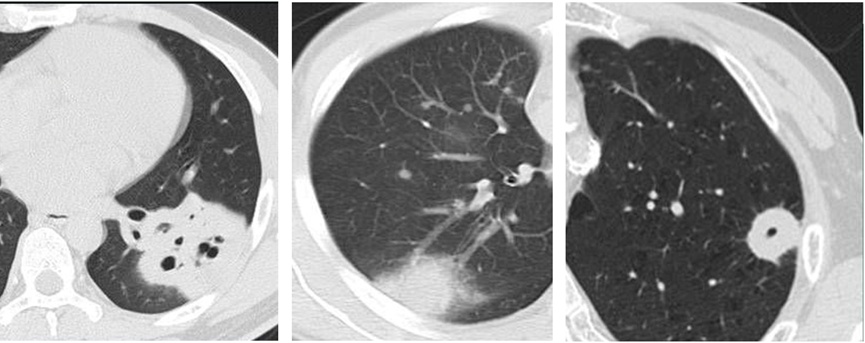

右上肺一枚磨玻璃结节随访过程中变成混杂密度磨玻璃结节(内有分叶、毛刺和空泡),最后进展为一实性肿块

- 结节形态与边界:良性结节往往形态规则、边界清晰;恶性结节可能形态不规则、边界模糊,还可能出现毛刺征、分叶征、空泡征等形态学特征。

- 结节与周围结构的关系:观察结节与周围血管、支气管等结构的关系,如血管集束征、支气管充气征等,有助于评估结节的恶性风险。